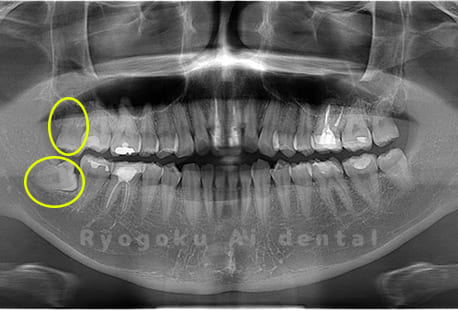

Case01

- 原因

- 水平埋伏智歯

- 治療内容

- 下顎の水平埋伏智歯を抜歯

<リスク・副作用>

手術後は痛み、腫れ、痺れなどの副作用が生じる場合があります。